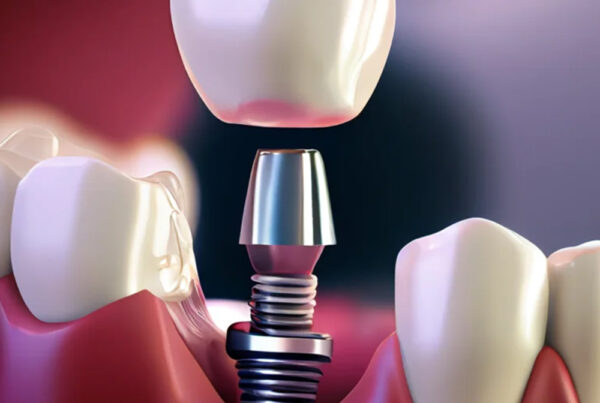

Zirkonyum kuron, olağanüstü gücü ve estetik nitelikleriyle bilinen bir malzeme olan zirkonyum oksitten yapılan bir diş kuronu türüdür. Bu kuronlar hasarlı, çürümüş veya zayıflamış dişleri kaplamak, şekillerini, boyutlarını ve işlevlerini geri kazandırmak için kullanılır. Ayrıca diş implantı restorasyonunun bir parçası olarak veya rengi solmuş veya şekilsiz dişlerin görünümünü iyileştirmek için de kullanılabilirler.

- Diş İmplantları: Eksik bir dişin yerini almak için bir diş implantının üzerine yerleştirilen bir kron olarak.

- Kuron Yerleştirme: Kuron hazır olduğunda, hazırlanan dişin üzerine yapıştırılarak işlevi ve görünümü geri kazandırılır.